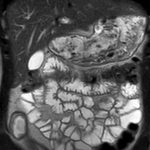

Une préparation orale sera à boire une heure avant l’entrée dans la machine et avant certains examens (telle qu’une entéro-IRM ou une bili-wirsungo-IRM) pour effacer le signal liquidien des structures digestives qui gênent l’analyse des voies bilio-pancréatiques.

Ce type d’exploration s’intéresse au foie, aux surrénales, aux reins, au pancréas, à la rate et au péritoine